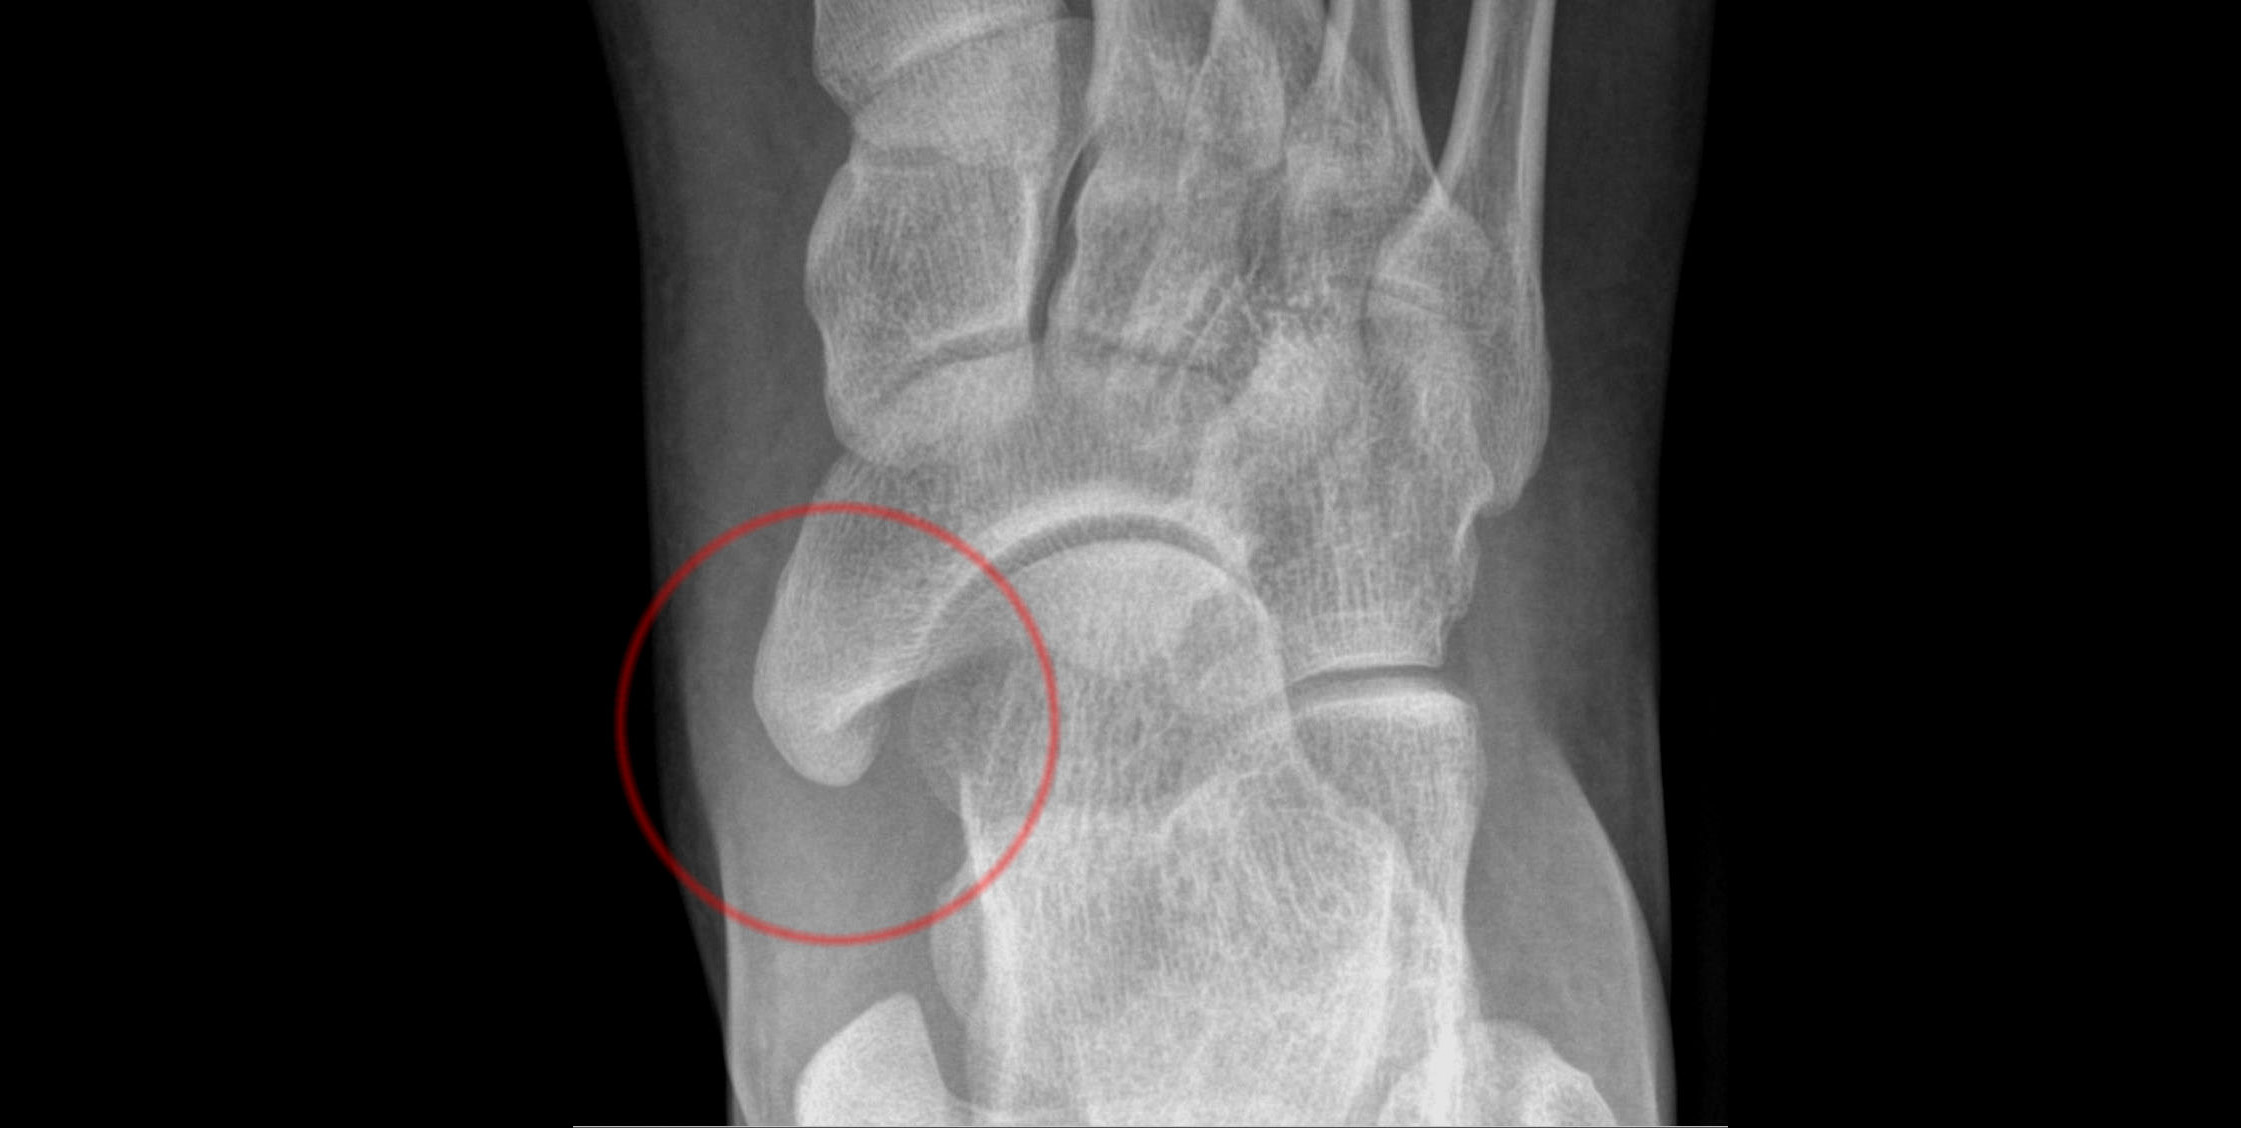

Dodatkowa kość łódkowata

W większości przypadków wada nie daje żadnych dolegliwości, a jej wykrycie jest przypadkowe w trakcie prześwietlenia stopy z innych powodów. Jednakże u niektórych osób w okresie dojrzewania może pojawić się wyczuwalny po stronie przyśrodkowej stępu guz. Bywa on bolesny i może powodować trudności w doborze obuwia. Rozpoznanie stawia się na podstawie badania radiologicznego.

Rozróżnia się trzy typy tej wady:

- Typ I – przeważnie asymptomatyczny. To niewielkiego rozmiaru kostka dodatkowa położona ku tyłowi.

- Typ II – wyraźna kostka dodatkowa w przedłużeniu kości łódkowatej.

- Typ III – przerośnięta kość łódkowata układająca się w kształt rogu.